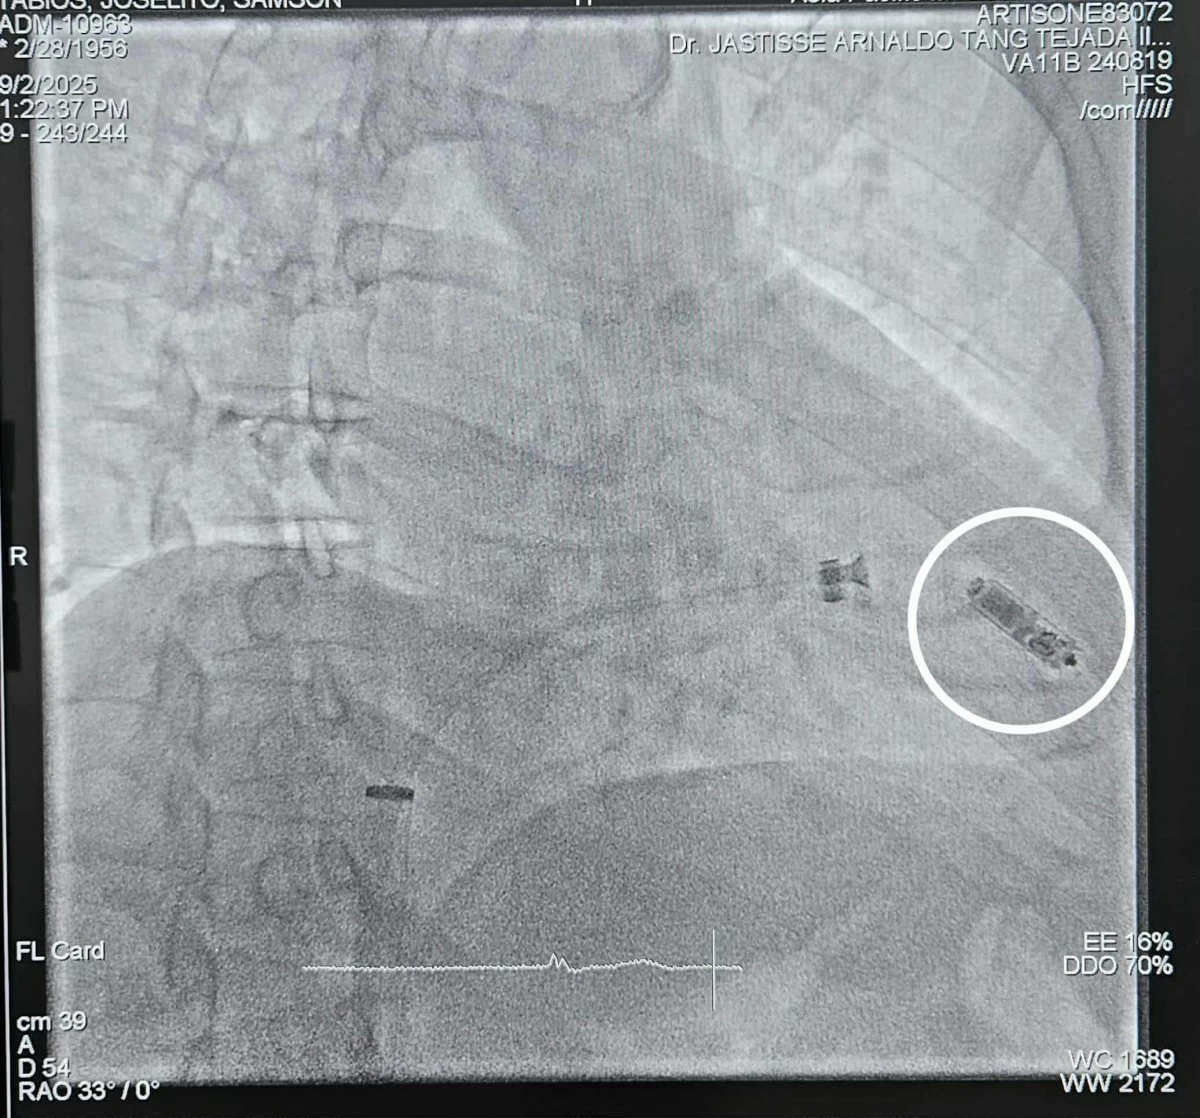

Western Visayas marked yet another achievement in the field of advanced and minimally invasive surgery, as a team of Aklan-based doctors has successfully implanted the first leadless pacemaker in the region using the Micra, considered the world's smallest pacemaker.

The team of doctors from the Asia Pacific Medical Center-Aklan --- headed by Dr. Claire B. Perez (Adult Cardiologist) as the attending physician and Interventional cardiologist, Dr. Jastisse Arnaldo T. Tejada III (Asia Pacific Medical Center-Aklan & Perpetual Help Medical Center-Las Pinas), Dr. Douglas Bailon (St. Luke's Medical Center-BGC), anesthesiologist Dr. Francis Stemar B. Villaruel, and endocrinologist Dr. Gregory Joseph Ryan Ardena --- implanted the device on a 69-year-old male diagnosed with sick sinus syndrome, a heart condition where the sinoatrial node doesn't function properly, leading to abnormal heart rhythms and symptoms like dizziness, syncope or loss of consciousness.

Roughly the size of a large vitamin capsule, the Micra is almost invisible once in place, giving patients the benefit of advanced technology without the visible signs and complications of surgery. Unlike the conventional pacemakers that require a surgical "pocket" in the chest and wires connected to the heart, the breakthrough device is implanted directly inside the heart through a small entry into the vein in the leg. This minimally invasive procedure allows patients to recover faster and have a lower risk of infections. Aesthetically, it leaves no visible surgical scar compared to traditional pacemaker implants.